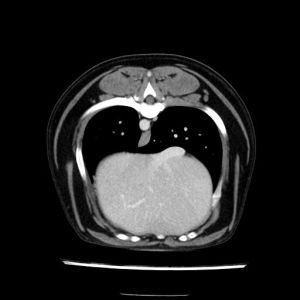

La lesione focale epatica , la ceus,la Tac e il chirurgo .